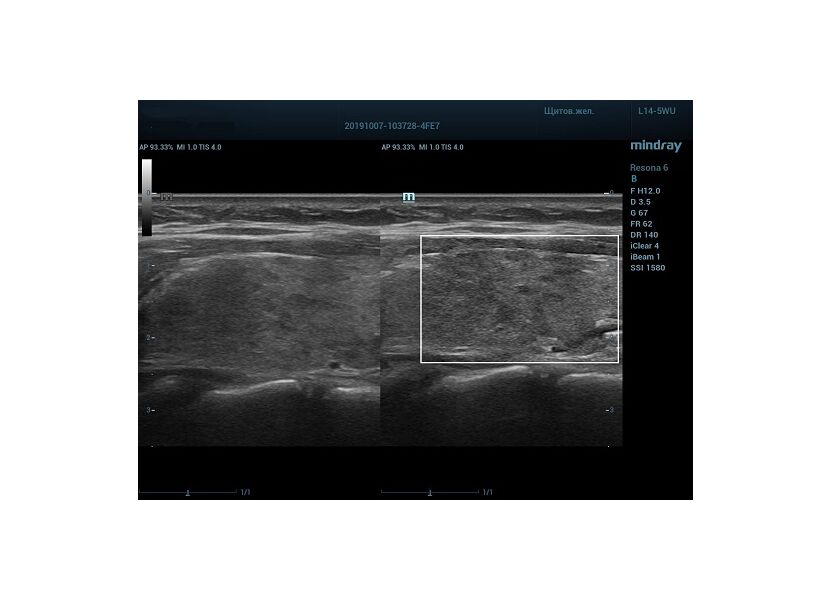

HD Scope позволяет достигать поразительной разрешающей способности выбранной зоны сканирования, при этом улучшая как детализацию, так и контрастность изображения. Помимо пространственного разрешения мы получаем преимущество и по разрешению во времени. Прибор получает огромное количество нативных изображений практически одновременно, и при сборе итоговой картины не происходит смещения объекта под датчиком, а значит и нет размывания изображения. Все участки раздела фаз, каждый контур образования теперь видны, мы все ближе к идеальной картинке.

Как он работает? Особенностью платформы ZST+, на которой построены приборы Mindray Resona, является так называемое многолучевое сканирование. В отличие от обычного датчика, который получает изображение в виде прямого эхо, датчики приборов этой серии проводят многолучевое сканирование каждым элементом с огромной скоростью, получая огромное количество данных. Затем происходит сложная постобработка и сбор из множества «многолучевых» снимков идеальной картинки.

Вторая особенность ультразвуковых машин данной линейки — это изменение расчетных констант распространения ультразвука, таким образом прибор перебирает для каждой ткани свои значения скоростей волны и пересчитывает каждую точку, делая менее выраженным поглощение по глубине. Эти особенности позволили использовать без фокусные технологии сканирования. Функция HD Scope позволяет использовать эти ресурсы для исследование небольшой области, значительно увеличивая качество изображения.